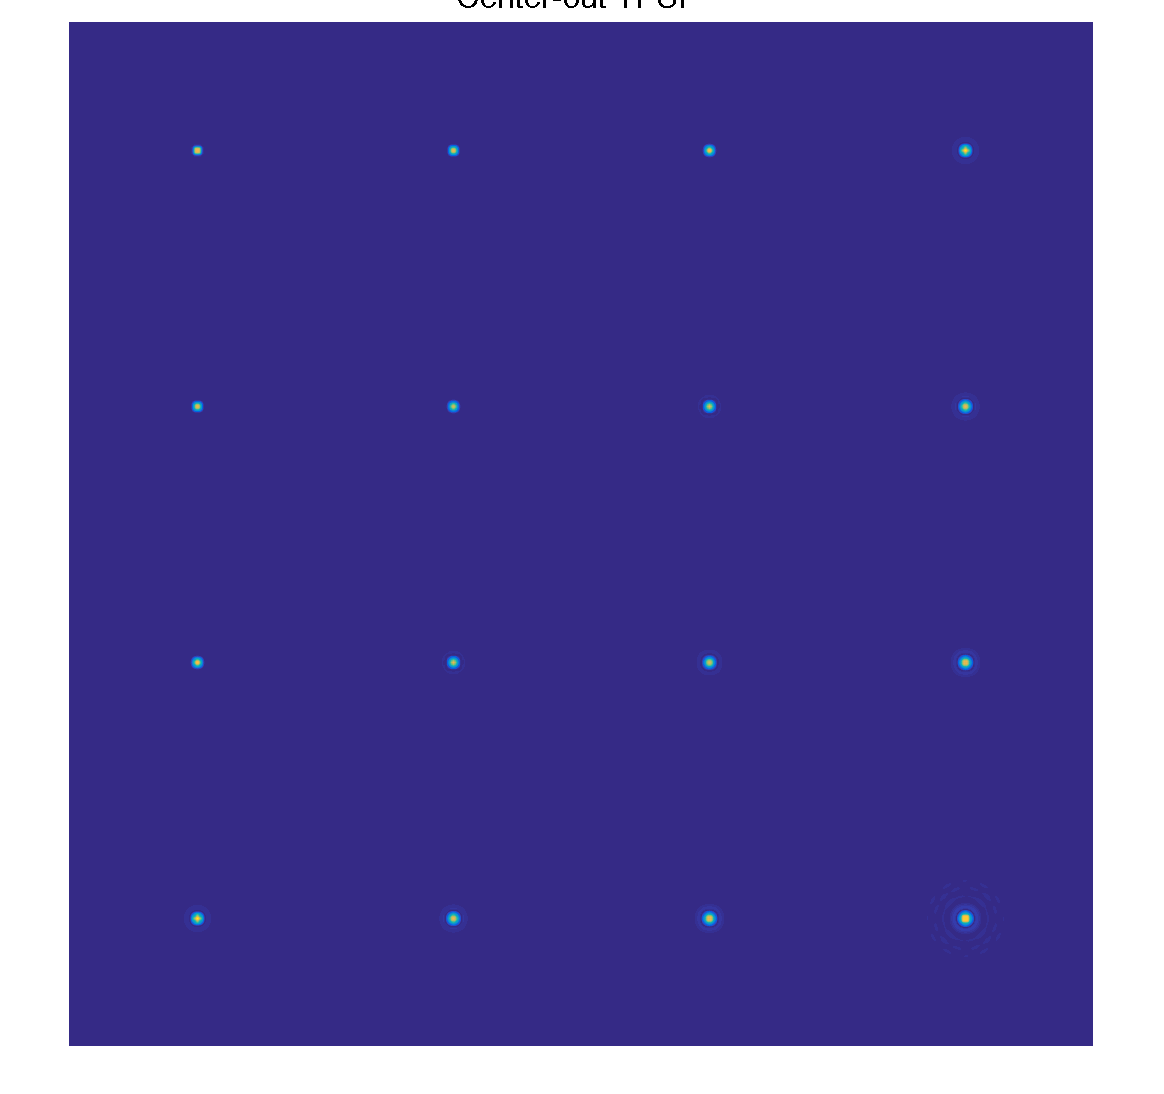

Simulate center-out ordering

The TPSF from center-out ordering shows blurring, and the coefficients are coupled

mask_options.shuffle = false; mask = gen_t2shuffling_mask(mask_options); TPSF_cent = tpsf(mask, basis, K, patch_size); figure(2); imshow3(TPSF_cent), colormap('default'); ftitle('Center-out TPSF', 32);